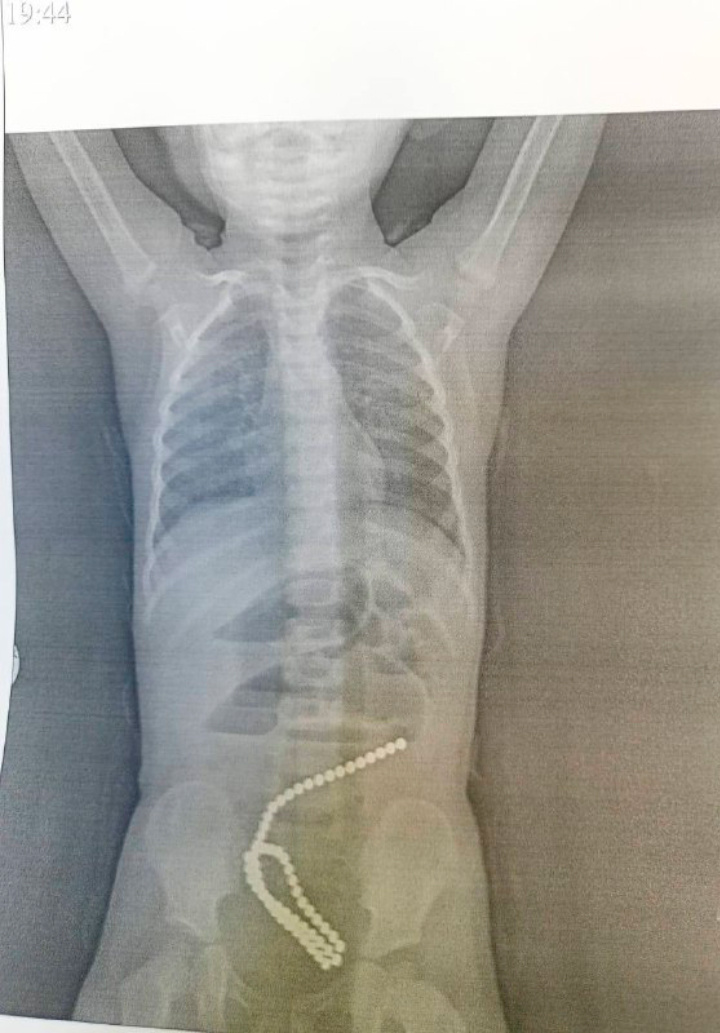

Врачи опешили, увидев рентген-снимок ребенка. В его животе нашли 60 магнитов - фото

В отделение детской хирургии Комсомольска поступила маленькая девочка. По словам родителей, малышка жаловалась на сильную боль в животе. Когда ребенку сделали рентген, оказалось, что в кишечник попали 60 магнитных шариков.

Маленькая пациентка провела почти два часа на хирургическом столе. Во время операции врачам удалось извлечь яркие магниты, похожие на бусы.

- У девочки инородные тела вызвали кишечную непроходимость, повреждение стенок кишечника, - сообщил Андрей Костенко.